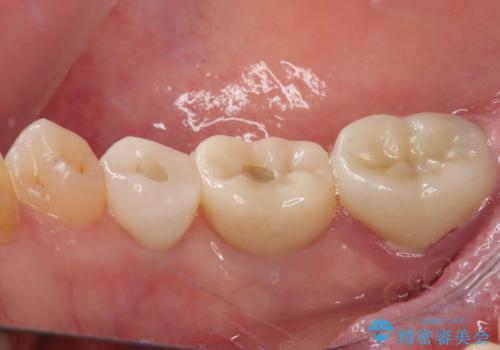

割れてしまった奥歯 インプラント治療

- 近医にて抜歯が必要と診断されたとのことで来院された患者様です。

術前の診査では、歯が破折している可能性が高いものの、確実に抜歯が必要と診断ができない状態でした。

状況次第では抜歯が必要となり、その際にはインプラント治療を行うことを了承いただいた上で、破折していない場合には根管治療を行うこととしました。

土台の材料を外して顕微鏡下で確認したところ、歯根にまで及ぶ破折が認められたため、インプラント治療を行うこととしました。

インプラント治療をきっかけに、銀歯を全てセラミックに替えていきました。